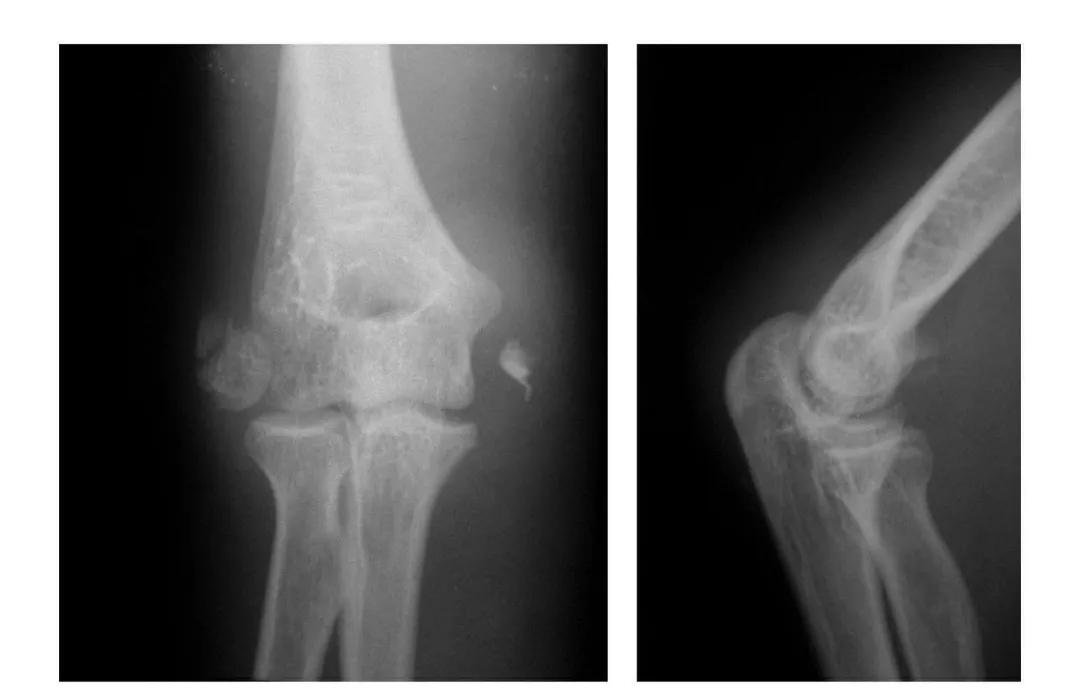

肱骨小头冠状面骨折

(一)完全骨折

本病亦称哈-斯(Hahn-Steinthal)型骨折

例1:肱骨小头基底部呈冠状面骨折,骨折块呈半球状向肘前上方移位。

例2:肱骨小头基底部冠状面骨折,骨折块呈半球状向肘前移位并肱骨内上髁无移位骨折。

例3:肱骨小头及滑车桡侧壁前半部呈整体性冠状面骨折,骨折块向前上移位并外髁骨折。